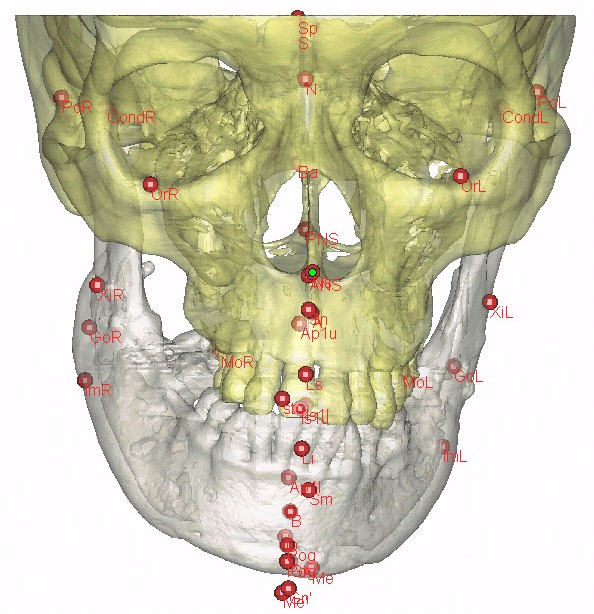

Bilgisayarlı Tomografi, MR, 3 Boyutlu Ultrasonografi gibi farklı görüntüleme tekniklerinin birleştirilmesi ile kişiye özel sert ve yumuşak doku uygulamaları ile sanal ameliyatlar, Kranio Maksillo Fasiel-CMF modulü ile pre-operatif verilerle hastanın post operatif yumuşak doku görüntülemesi, hastanın birebir ölçekli verileri ile 3 boyutlu (3B) katı modelleme ve bu modellerle tüm osteotomi ve distraksiyonun ameliyat öncesi model üzerinde tatbikatı, kişiye özel protez uygulamaları için pek çok ana bilim dalındaki hekim üç boyutlu görüntüleme yazılımı Mimics'i kullanmaktadır.

4C firmasının temsilciliğini yaptığı Mimics yazılım programı ve Z Corp. 3 boyutlu yazıcıları ile hastanın bire bir ölçekli katı modeli üzerinde tüm osteotomiler, vida, plak, distraktör uygulaması, yörüngelerininin doğrulanması, kişiye özel protez tasarımı mümkündür...